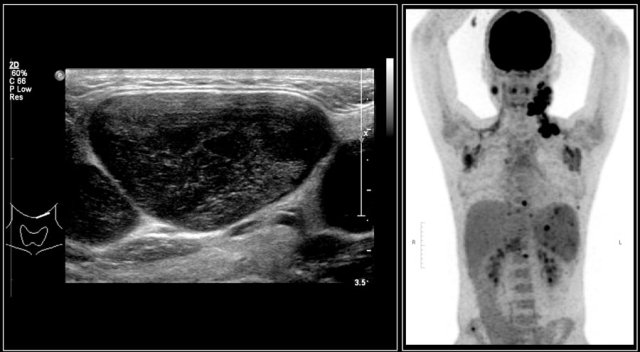

Malignant lymphoma presents with painless lymphadenopathy.

On ultrasound the affected nodes are round, homogeneously hypoechoic and the normal echogenic hilum is absent.

The diagnosis is made by ultrasound-guided biopsy or excision.

PET/CT will demonstrate the extension of the disease.

The images are of a fourteen-year-old boy with a painless swelling in the left neck.

The ultrasound shows several enlarged hypoechoic lymhnodes, that lack an hyper-echoic hilum.

Here another fourteen-year-old boy with a painless swelling in the left neck.

Ultrasound showed several enlarged lymhnodes.

Continue with the MR and PET/CT...

A coronal STIR image shows the pathologic lymph node masses similar to the PET-CT.

The diagnosis was Hodgkin's lymphoma.